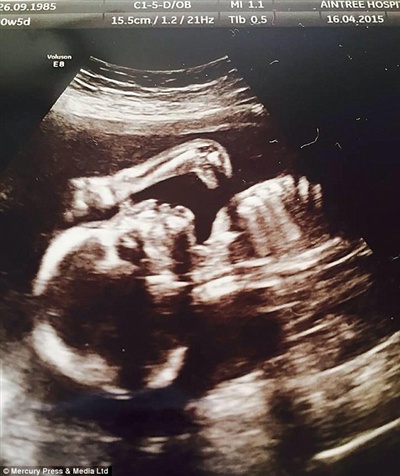

Một bà mẹ người Anh đã rất ngạc nhiên khi một vật thể lạ có hình của “chú khủng long” xuất hiện trong siêu âm thai của cô.

Leanna Sullivan vừa từ bệnh viện trở về sau khi khám thai. Cô đang rất mong chờ đứa con đầu lòng của mình – cô con gái Ruthie-Lou chỉ còn 5 tuần nữa sẽ chào đời. Nhưng cô không thể ngờ được một “sinh vật lạ” thời tiền sử lại xuất hiện trong hình ảnh siêu âm thai 20 tuần của mình.

Leanne rất ngạc nhiên khi thấy chú khủng long trong hỉnh ảnh siêu âm của cô.

Lúc đầu, Leanna Sullivan đã không hề nhận ra bóng đen lạ trên hình ảnh của tờ giấy siêu âm khi cô mang chúng về từ bệnh viện vào tháng 4.

Những hình ảnh ghi lại trên siêu âm thai giống một loài khủng long ăn cỏ có cổ dài. Loài sinh vật chỉ tồn tại trong thế kỉ jura cả triệu năm về trước.

Và chỉ khi Leanne đưa hình ảnh này khoe với bạn bè và gia đình mình thì mới có người chỉ ra đặc điểm kì lạ trên ảnh cho cô và chồng cô – anh James Fletcher, 25 tuổi.

Cận cảnh 'con khủng long cổ dài' trong hình siêu âm thai của Leanne.

Cặp đôi này đã chia sẻ những hình ảnh trên lên mạng và bức hình đã nhanh chóng thu hút được sự quan tâm của rất nhiều người.